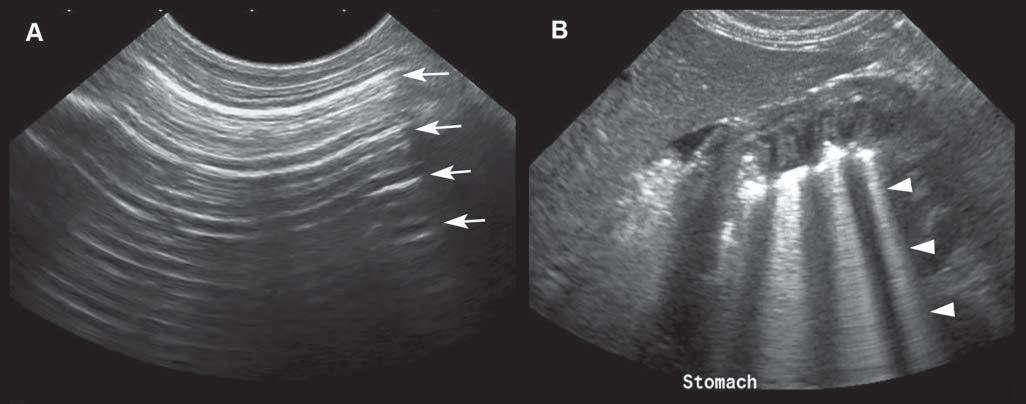

Reverberation

Reverberationartifactstypicallyappearasaseries ofmultiple,equallyspacedlines(Figure1.16A). Theyoccurwhenthebeamhitsahighlyreflective

interface–suchasanairpocket–andsendsitbackas anechoofsimilarintensity.Thehigh-intensityechois partlycapturedbytheprobe,producingahyperechoic lineatthepocket’sinterface,butwithnoechocoming fromdeepertissue.Thesurfaceoftheprobewillreflect thishigh-intensityechoandsenditbackandforth. Aspartoftheechoisperceivedeachtimeitreturns, thecomputercalculatesthetimethathaspassedsince theinitiallaunchofthewavepulseandthusrecords

severalequidistanthyperechogeniclines.Thereis decreasingechogenicityoftheinterfaceasitgoes deeper,duetoagraduallossofwaveintensitythat reboundsandisattenuatedduringitstrajectory.

Comettail isatypeofreverberationartifact–it appearsasaseriesofshortandverycloselyspacedsuccessiveechoes(Figure1.16B)thattypicallydecreasein intensityandwidthindepth.Whengasbubblesform thinlayersseparatedbyliquid–asinthedigestive tract–thewavesreboundbetweenthelayers,resulting inmanyechoesthatreturntotheprobeatregularintervals,makingatrailofechoesintheformofashadow resemblingacomet’stail.Thisartifactisalsoencounteredwithmetallicpelletsorsurgicalclips. Ringdown artifact similarlyappearsasaseriesofparallelreflectivelinesthattypicallyextendbehindagascollection. Ithappenswhenairbubblesresonateattheultrasound frequencyandthenemitreflections.Thiscanbeseen associatedwithirregularlungsurfaces,gastrointestinaltract,andabscesses.Practically,comettailandring downartifactsappearverysimilaronthescreen,even thoughtheyresultfromdifferentphysicalinteractions.